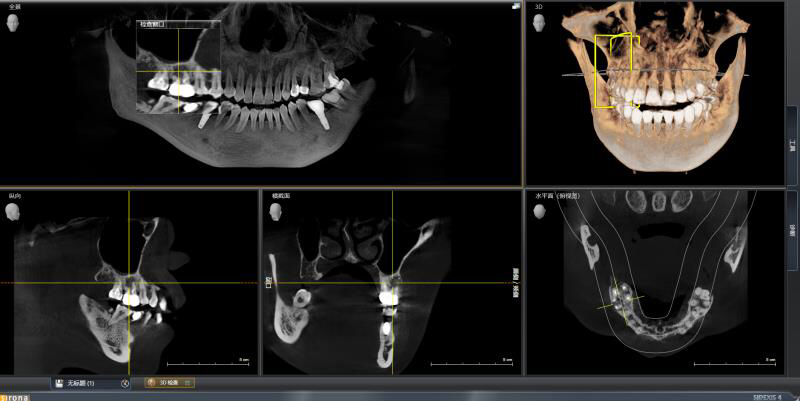

患者中年女性,右上6外院根管治疗多年,近期牙龈红肿,咀嚼疼痛,X线检查见根尖区大面积低密度影响,怀疑有遗漏的根管没有清理,用铒激光无损拆掉牙冠后进行根管再治疗,找到了遗漏的MB2,妥善的根管治疗完成后,重新戴上之前拆掉的牙冠,即解决了疼痛又为患者节省了一笔费用。